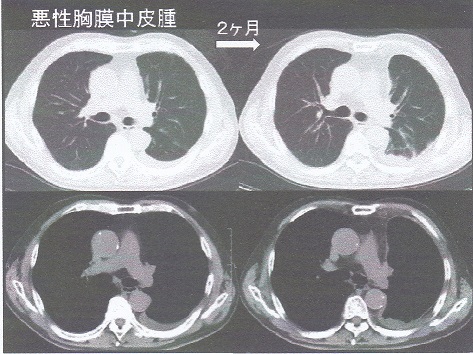

悪性胸膜中皮腫は縦隔側の胸膜肥厚が出てくる点でびまん性胸膜肥厚と異なるので、びまん性胸膜肥厚患者の経過観察中で縦隔側の胸膜肥厚を認めた際には、悪性胸膜中皮腫の合併を考え、精査をする必要がある。